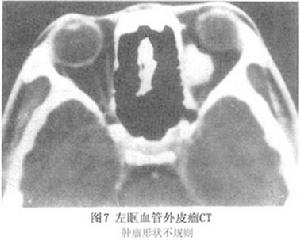

3.CT掃描 CT顯示腫瘤為高密度塊影,位於肌肉圓錐內或外,類圓形或形狀不規則,邊界清楚,內密度均勻CT值+30~+67HU,平均+50HU。注射造影劑後有明顯強化,CT值可達138HU如此高的增強值在其他腫瘤少見。這一方面說明腫瘤內血管豐富,血流記憶體留的造影劑較多;另方面由於血-組織屏障破壞,造影劑自血管內滲出較多。惡性血管外皮細胞瘤除形狀不規則、高度強化之外,尚可侵蝕眶壁。